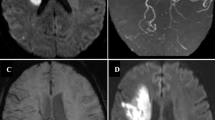

In our study, we have demonstrated the presence of asymmetric, numerous, and large vessels over the ipsilateral cerebral hemisphere in more than half of the patients with carotid occlusion. Such a finding was not observed in any of the patients with critical carotid stenosis. A clarification is needed here as to whether these vessels represented prominent veins or whether they are arterial collaterals that occur in occlusive states. These vessels were assumed to be veins based on following premises. First, as the severity of carotid occlusion increases, the CBF progressively declines and OEF increases as a compensatory mechanism to maintain the CPP. Due to maximal extraction of oxygen by ischemic tissue, deoxyhemoglobin concentration and deoxy- to oxyhemoglobin ratio increases in the draining veins [7]. This induces susceptibility effect detectable with sequences such as SWI. Indeed, the initial application of SWI was to evaluate the small intracranial veins independent of arteries [11]. The FLAIR vascular hyperintensity (FVH) sign described in carotid stenosis, occlusion, or acute infarction has been shown to correlate with collateral flow, and this is thought to be secondary to slow sluggish flow within the collaterals [18, 19]. Authors’ personal experience with acute ischemia and moyamoya diseases showed that patients with exuberant collaterals had normal finding in SWI sequence (Fig. 3). Liebeskind suggested that augmented extraction of precapillary oxygen by adjacent brain tissue leads to elevation of intravascular deoxyhemoglobin with in the collaterals and this in turn could be detected by gradient MR as blooming [20]. Secondly, these vessels show no territorial preferences unlike arteries and are visualized either over the entire cerebral hemisphere or are localized to the regions collaterals are less expected.

Axial T1 (a), Axial FLAIR (b), contrast enhanced MRA (c), SWI (d) and contrast enhanced T1 (e, f) in a patient with bilateral supraclinoid carotid and distal basilar occlusion with moyamoya pattern and exuberant collaterals. Note the multiple collaterals in the contrast enhanced MRA and T1 images. However, the SWI images do not show prominence of blood vessels